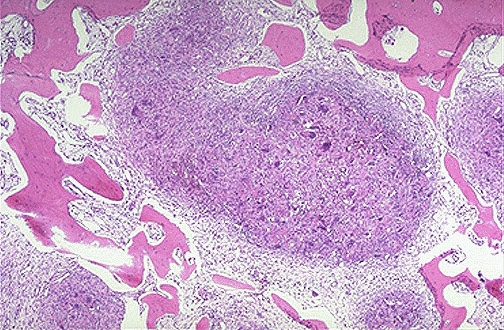

| Here is a "brown tumor" of bone in a patient with hyperparathyroidism. The high parathormone levels increase osteoclast activity in bone and produce irregular bone resorbtion with microfractures and hemorrhage and macrophage proliferation and fibrous connective tissue proliferation. |